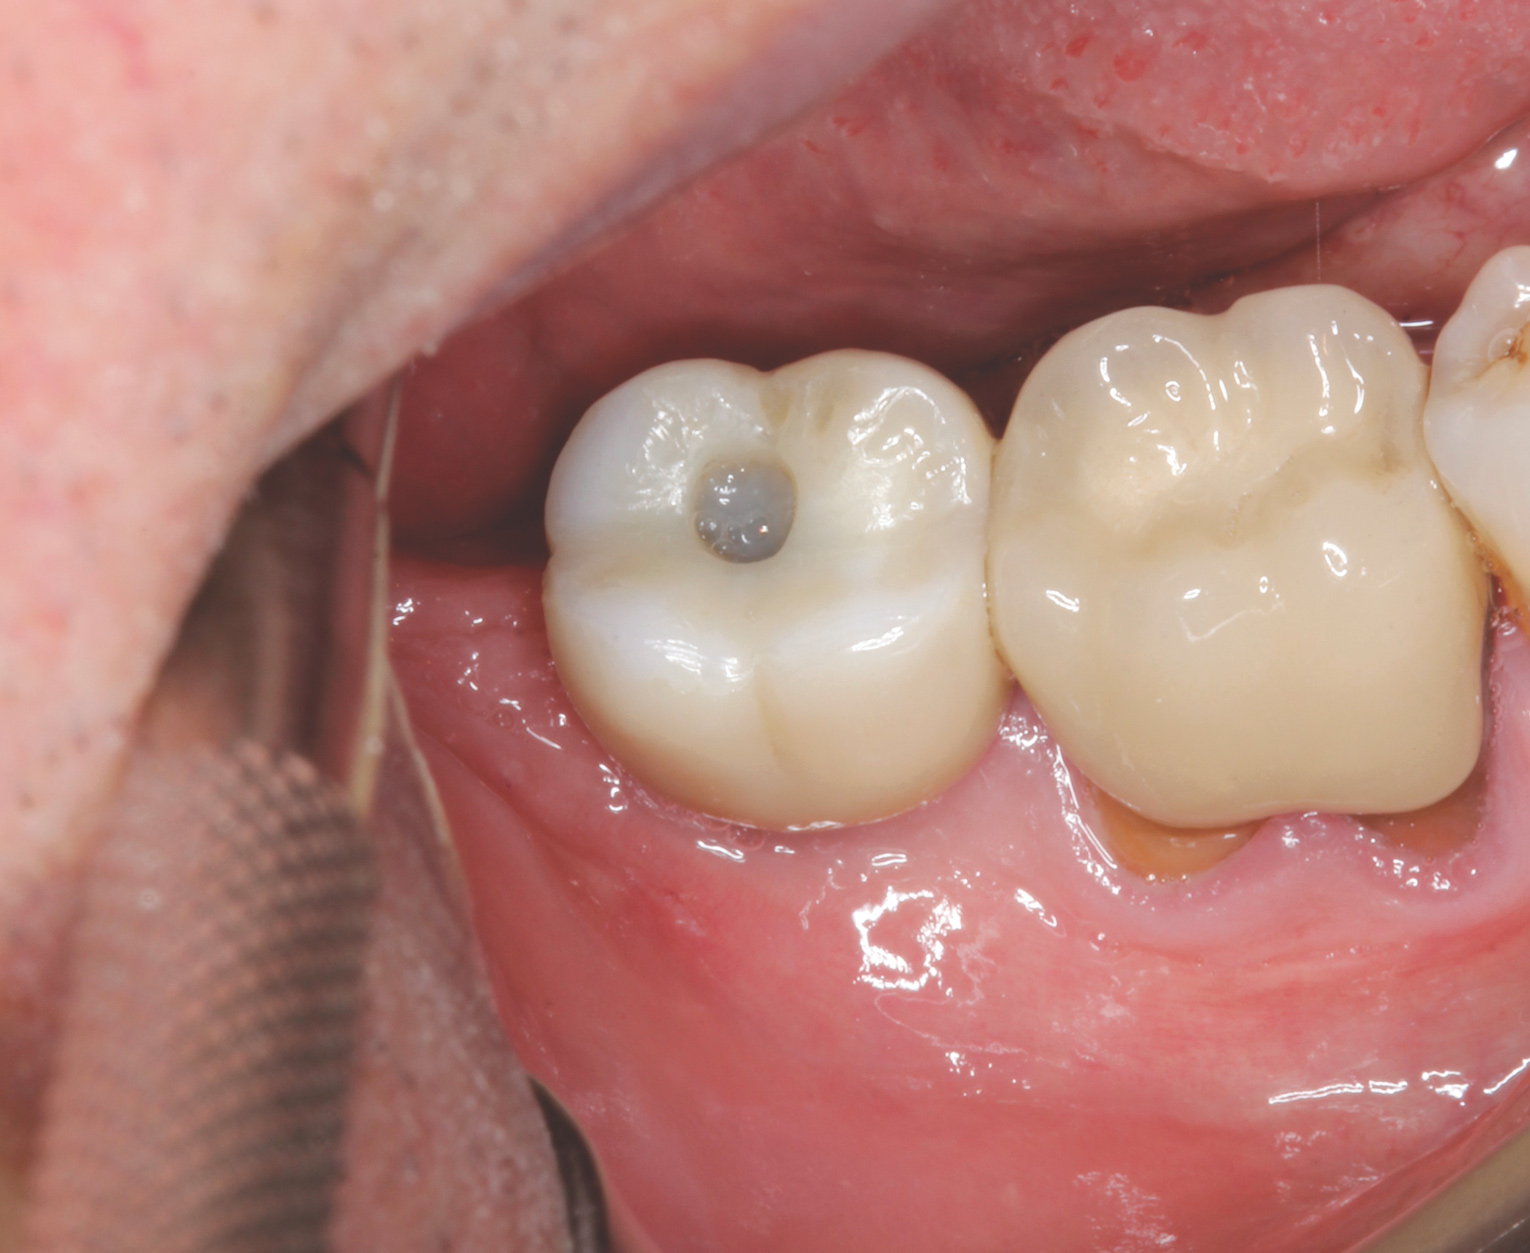

Implant insertion (5.5 mm x 13 mm NobelActive®, Nobel Biocare, nobelbiocare.com) gave excellent primary stability, was level with the residual buccal bone, and achieved an ISQ reading of 74 (Figure 14). Lingual bone contouring (to avoid abutment impingement) was followed with implant gap grafting, which included the mesiobuccal root defect and adjacent extraction site, using mineralized particulate cortico-cancellous allograft (enCore®, Osteogenics Biomedical). A 7 mm x 8 mm poly-ether-ether-ketone (PEEK) healing abutment was inserted and the access opening filled with PTFE tape (Figure 15). A single layer of dHACM (Figure 16) was inserted on the bone graft with tissue forceps and saturated with saline to seal the implant-soft-tissue interface. Suturing with 4-0 chromic gut secured the site, using inverse "figure 8" at the anterior and interrupted sutures at the posterior margin (Figure 17).

Fig 15. Grafting with particulate mineralized cortico-cancellous allograft and placement of PEEK healing abutment.

Figure 15

Fig 18. Healing at 4.5 months, occlusal view.

Figure 18